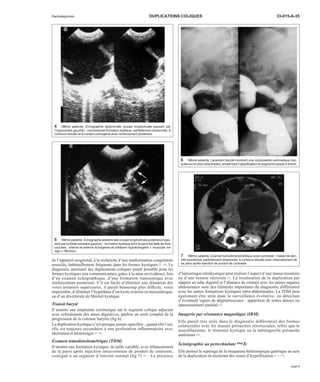

4 Même patiente. Échographie abdominale (coupe longitudinale passant par

l’hypocondre gauche) : volumineuse formation kystique, partiellement cloisonnée, à

contours lobulés et à contenu échogène avec renforcement postérieur.

5 Même patiente. Échographie abdominale (coupe longitudinale postérieure pas-sant

par la fosse lombaire gauche) : formation kystique dont la paroi est faite de trois

couches : interne et externe échogènes et médiane hypoéchogène « muscular rim

sign » (flèches).

Échographie

Elle montre une formation kystique anéchogène, avec renforcement

postérieur en cas de contenu liquidien, ou une masse échogène avec

renforcement postérieur en cas de contenu mucoïde ou d’hémorragie

(fig 4). Un liseré interne échogène (muqueux) séparé d’une limite

externe hyperéchogène par un autre liseré hypoéchogène (couche

musculaire) (fig 5) serait un aspect très évocateur du diagnostic de

duplication kystique « muscular rim sign » ; ceci le différencie du reste

des masses kystiques intra-abdominales de l’enfant telles que kystes du

mésentère et de l’épiploon, kystes de l’ovaire, diverticule de Meckel

kystique, kyste omphalomésentérique ou kyste de l’ouraque [1, 5].